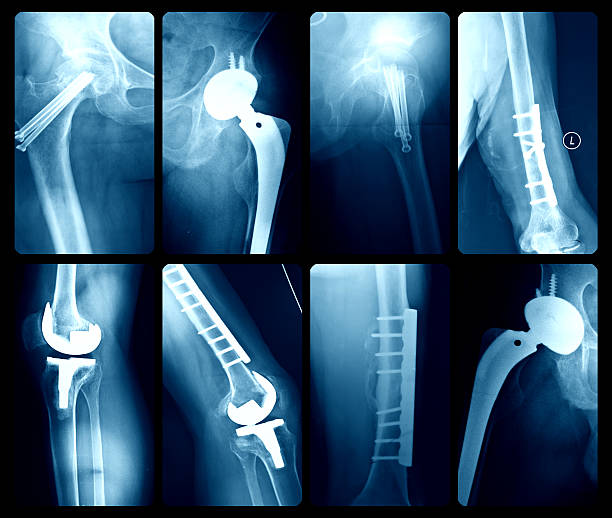

Orthopaedic Surgery

Orthopaedic Surgery